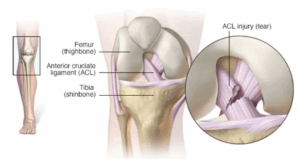

Acl injury

An ACL injury is a tear or sprain of the anterior cruciate (KROO-she-ate) ligament (ACL) — one of the strong bands of tissue that help connect your thigh bone (femur) to your shinbone (tibia). ACL injuries most commonly occur during sports that involve sudden stops or changes in direction, jumping and landing — such as soccer, basketball, football and downhill skiing.